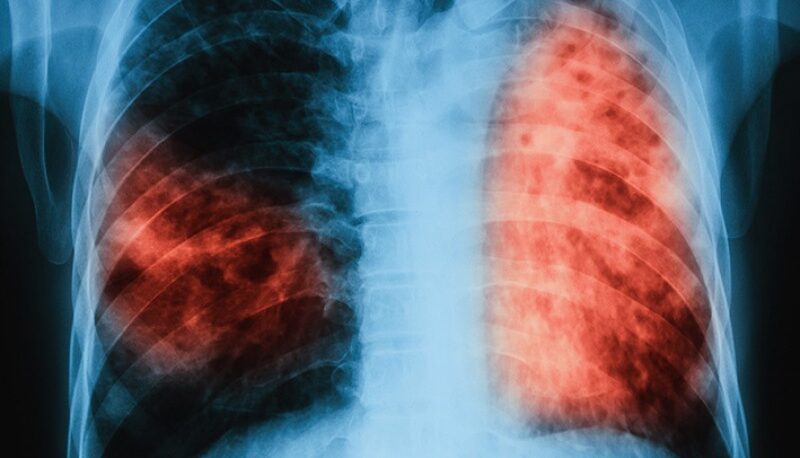

El neumonólogo Andrés Burke Viale, miembro de la Asociación Argentina de Medicina Respiratoria, confirmó en diálogo con Radio Social Club que los casos de tuberculosis están en aumento en todo el país. Según precisó, la situación también se refleja en la provincia de Misiones, donde se han reportado más diagnósticos en los últimos meses.

“Hay aumentos de casos a nivel nacional, y en Misiones también hubo aumento”, señaló el especialista. Además, detalló que los más afectados son los varones, especialmente aquellos en edades jóvenes: “La estadística muestra que los hombres son los más afectados. Se ve un aumento importante de casos en edades entre 15 y 40 años”.

Comparando los primeros trimestres interanuales, el profesional destacó que se produjo un aumento del 38% en los casos reportados, lo cual genera preocupación entre los especialistas del área respiratoria.